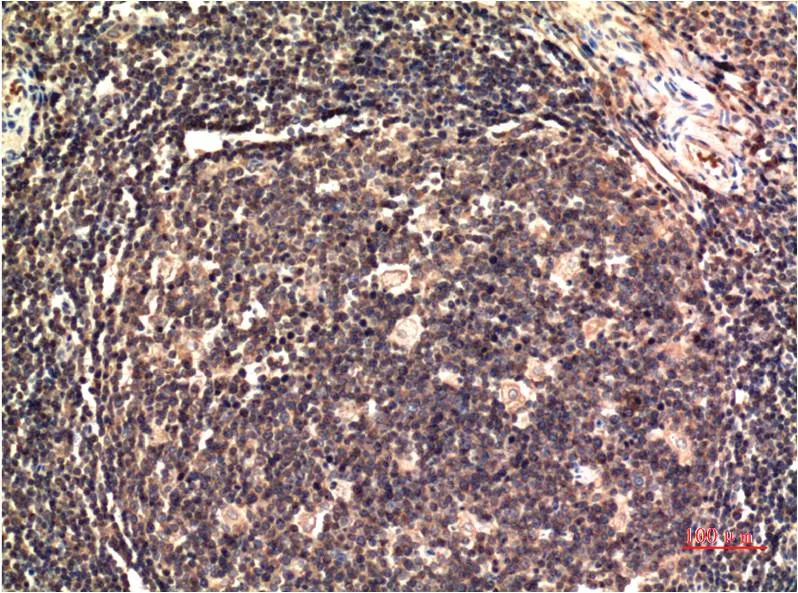

JAK2 (6B4) Mouse Monoclonal Antibody

Cat: AMM00767

Application:IHC-P

Reactivity:Human,Rat,Mouse

Conjugate:Unconjugated

Gene Name:JAK2